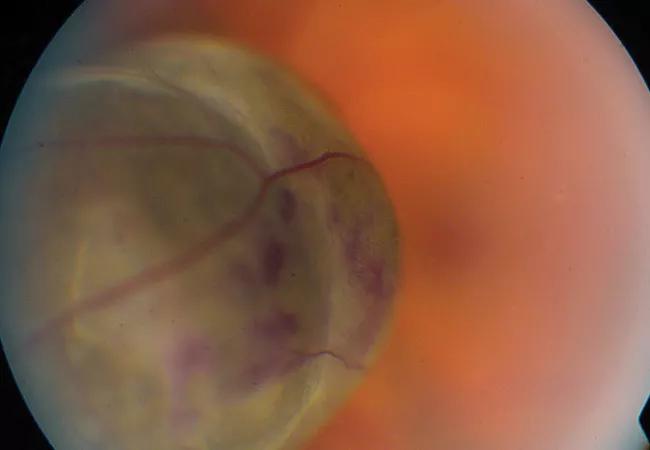

Cleveland Clinic Researchers Affirm Reliable Approach to Detecting Uveal Melanoma Metastases Without Biopsy

A retrospective cohort study of uveal melanoma patients at Cleveland Clinic’s Cole Eye Institute found that surveillance with hepatic ultrasonography (USG), followed by confirmatory scans, is highly likely to detect asymptomatic metastases. Researchers found that hepatic USG used for surveillance every six months, when followed by confirmatory scans, yielded a sensitivity and negative predictive value of 96 percent and 99 percent, respectively, for identifying asymptomatic metastases. This was reported in their research paper, published in JAMA Ophthalmology in December 2015 (Maria Choudhary, MD, Todd Emch, MD, Akshay Gupta, BS and James Bena, MS, Arun Singh, MD).

Patients who undergo treatment for uveal melanoma have the highest risk for metastases within the first five years after treatment — and most of these metastases occur in the liver. With the availability of highly accurate prognostic testing for uveal melanoma and a trend toward adjuvant therapy, systemic staging at baseline followed by periodic surveillance for metastases is an increasingly important management strategy, researchers said.